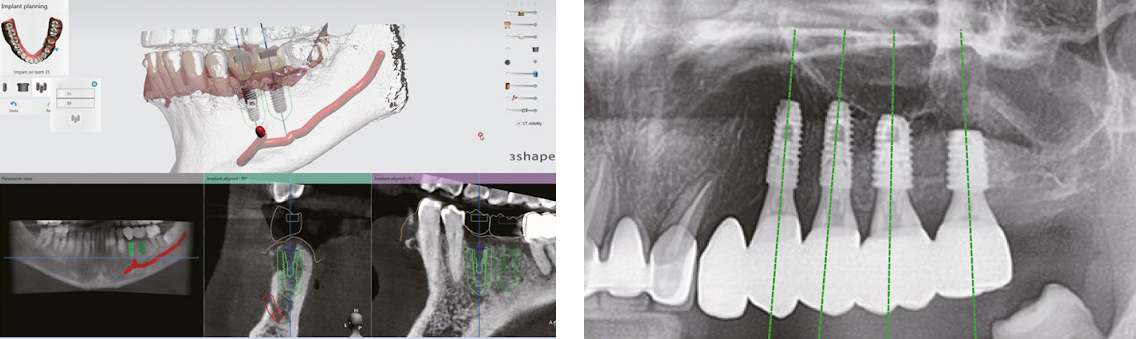

デジタルワークフローを通した安全・正確なガイドサージェリー

1段階:CTによる3D診断CTを活用した3D診断。

骨、歯肉、神経を総合的に考慮し、精密な診断を実現します。デジタルシミュレーションに骨の細部まで正確に診断可能となります。

CTを使用することにより、血管や神経の位置の正確な診断ができます。さらに2次元の一般的なレントゲンより、精密な診断ができ、手術の成功率も上がります。

2段階:デジタルデータによるシミュレーション

デジタルデータで手術計画を作成します。シミュレーションを通し最適位置を設定し、患者様専用のサージカルガイドを製作して手術を行います。デジタルシミュレーションにより骨の見えない部分や神経まで、詳細に診断でき、正確なインプラント埋入の位置、方向を決めることができ安全に手術が行うことが出来ます。

3段階:サージカルガイドを利用したインプラント手術

口腔内に装着したサージカルガイドで計画通りの安全で正確な手術を実施します。作製した、サージカルガイドを使用して手術をする為、時間短縮ができ、安全にインプラント埋入が可能です。